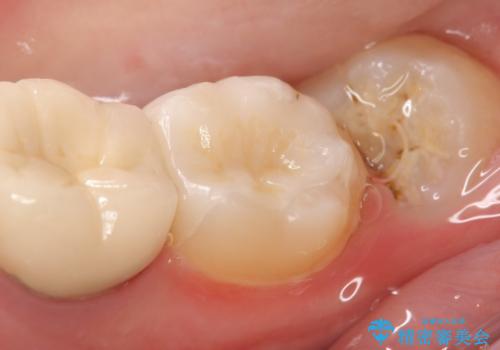

- 右下7の銀歯を白くしたいといらっしゃった方の症例です。

銀歯及び虫歯を除去後、セラミックインレーで修復を行いました。